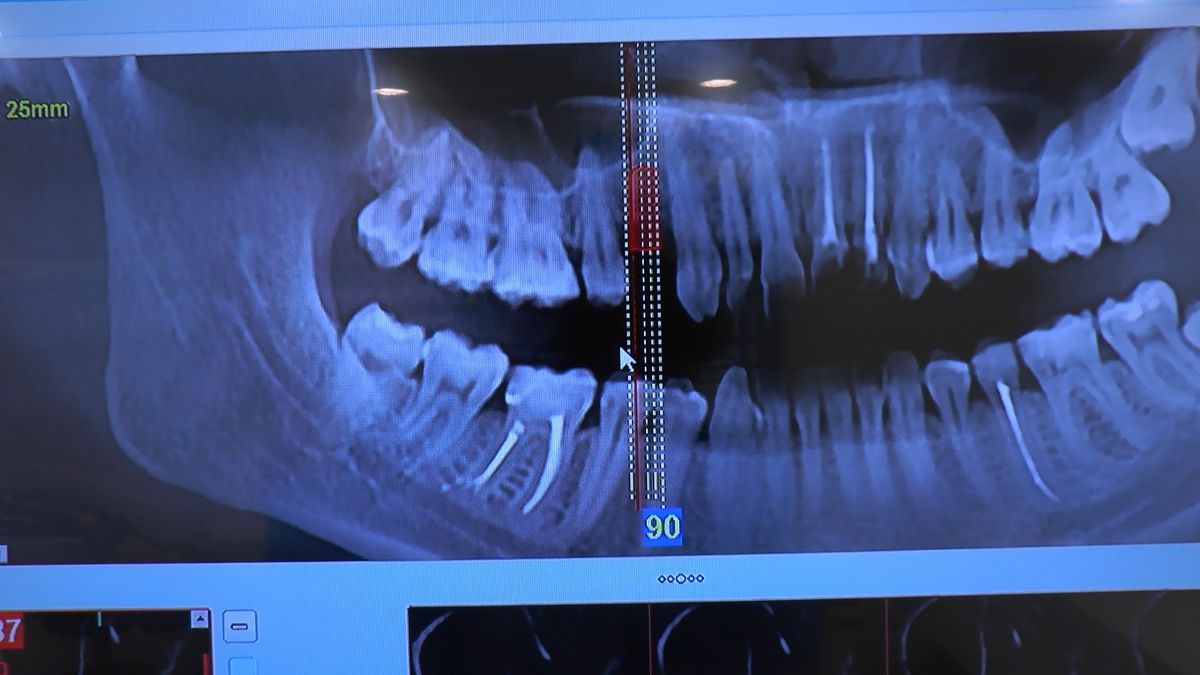

W ostatni weekend czerwca 2018 roku kursanci II Sezonu Preludium Implantologii odbyli piątą, finałową sesję, która w całości podporządkowana była praktyce. W ciągu dwóch dni zabiegowych Lekarze uczestniczący w szkoleniu przeprowadzili szereg zabiegów pod kierunkiem dr n.med. Violetty Szycik. Wszczepili 17 implantów oraz przeprowadzili ekstrakcje i zabiegi regeneracyjne kości. Zabiegi były wykonywane także w sedacji dożylnej z udziałem specjalisty anestezjologii i intensywnej terapii dr Jolanty Grzybowskiej. Preludium implantologii to nowy program edukacyjny dla adeptów implantologii stomatologicznej, którego celem jest wprowadzenie do implantologii poprzez pozyskanie wiedzy w szerokim zakresie i uwzględnieniem szczegółów mających decydujące znaczenie dla powodzenia leczenia implantologicznego. Ale tak jak wszystkie szkolenia w Instytucie Vivadental, w tym wiodące Practiculum Implantologii, zorientowane jest na praktyce i samodzielnym wykonywaniu zabiegów pod kierunkiem Mentora. To najlepsza edukacja w medycynie zabiegowej, a zarazem najlepszy start do implantologii.